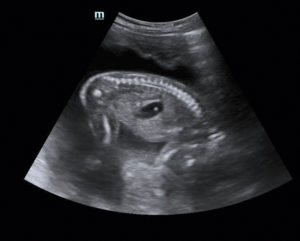

Когда делают третье плановое УЗИ, смотрят как состояние малыша, так и состояние органов матери, обеспечивающих жизнедеятельность плода. В III триместре плод достаточно развит, чтобы появилась возможность оценить строение его органов и определить возможные пороки.

Процедура УЗИ в третьем триместре дает возможность врачам подготовиться к рождению малыша, с целью немедленного врачебного вмешательства, если определяется какая-либо патология. Большое значение имеет развитие органов дыхания, так как способность дышать, а, следовательно, и жить, зависит от состояния легких.

- В обязательном порядке исследуют строение и функциональность внутренних органов. Оценивают работу головного мозга, мочевыводящей системы, сердца и остальных органов. Поскольку малыш уже большой, заметить любые отклонения гораздо проще, нежели на раннем сроке.

- Если диагностируются несовместимые с жизнью отклонения, до начала родов женщина направляется в специальное родовое отделение с надлежащим оборудованием. А после родов малышу предоставляется требующая помощь.